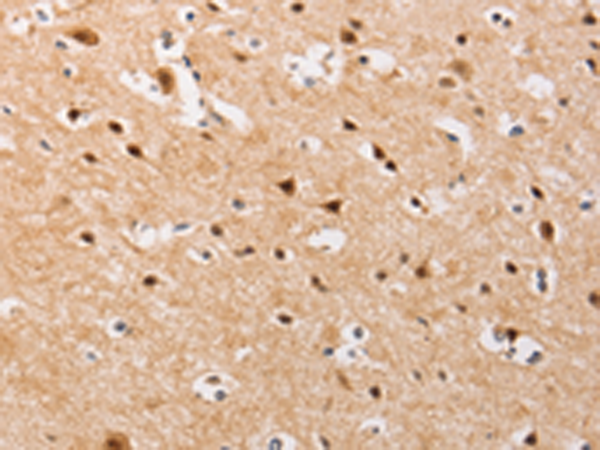

分类: 科研抗体货号: P07970别名: IDH; IDP; IDCD; IDPC; PICD应用: WB,IHC反应种属: Human, Mouse, Rat